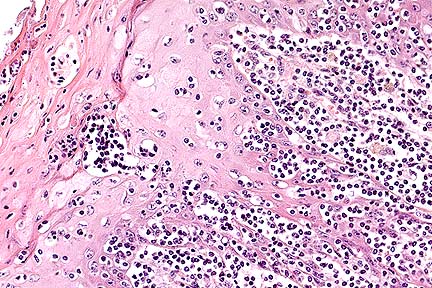

Mild to moderate non-suppurative myelitis with axonal swelling and degeneration. There is accumulation of amyloid protein around the vessel seen here in longitudinal section. (HE, 200X, 56K)

Cross section of a vessel whose wall is largely effaced by amyloid. The myelitis is very prominent in this photomicrograph. (HE, 200X, 63K)

Contributor's Diagnosis and Comments: In locally extensive areas of the spinal cord (S1), corresponding to the areas where the gross lesions were identified, there are large numbers of lymphocytes and macrophages, with local infiltrates of neutrophils and isolated eosinophils surrounding leptomeningeal vessels and extending into the subjacent neuropil of both the grey and white matter. Vessel walls, within both the white and grey matter, are infiltrated and surrounded by concentric accumulations of an eosinophilic, amorphous material which shows apple-green birefringence under polarized light after Congo-red staining (amyloid). Within some sections, there is an extensive accumulation of amyloid surrounding the central canal. There is intense gliosis of both white and grey matter. Within the white matter there is extensive, multifocal axonal degeneration and large numbers of axon sheaths containing gitter cells. Within the grey matter there is neuronal satellitosis and neuronal degeneration and necrosis characterized by swollen neurons which show extensive chromolysis. Multifocally, within the meninges there are moderate perivascular accumulations of lymphocytes and plasma cells with smaller numbers of neutrophils (not evident in all sections).

The most severe necrotizing and inflammatory lesions with perivascular amyloid are centered around T1 and T2; however, a gradation of inflammatory lesions extends from C5-T4. A second small, less severe, focus of myelitis, which unilaterally involves the left ventral grey horn and extends into the white matter, is also present at L1-L2.

The lesions in the spinal cord are consistent with protozoal myelitis (Sarcocystis neurona); however, no protozoal cysts or individual zoites could be definitively identified in the sections examined. This may be the result of the extensive long term therapy with a folic acid antagonist. The extensive accumulation of perivascular amyloid in the spinal cord is a very unusual lesion. Cerebral perivascular amyloid is described in old dogs and is associated with neuronal senile plaques. The cerebral amyloid deposits in old dogs are immunoreactive for beta-amyloid protein found typically in human brain from patients with Alzheimer s disease. Spinal cord amyloid angiopathy has been described in the human literature but is considered a rare and unusual lesion. Amyloid deposition, usually of the AA type (serum amyloid protein), is not uncommonly found in other parenchymal organs (liver and kidney) associated with chronic inflammatory diseases, but to our knowledge has not been described in the CNS in horses. The exclusive localization of the amyloid to the areas of spinal cord with the most severe inflammatory lesions and not to other areas of CNS or parenchymal origins suggests that its genesis is likely secondary to the local inflammatory response. However, a genesis independent of the inflammatory lesion cannot be definitively ruled out.

AFIP Diagnosis: Spinal cord: Myelitis, nonsuppurative, diffuse, moderate, with axonal degeneration and perivascular and multifocal amyloid, Arabian, equine.